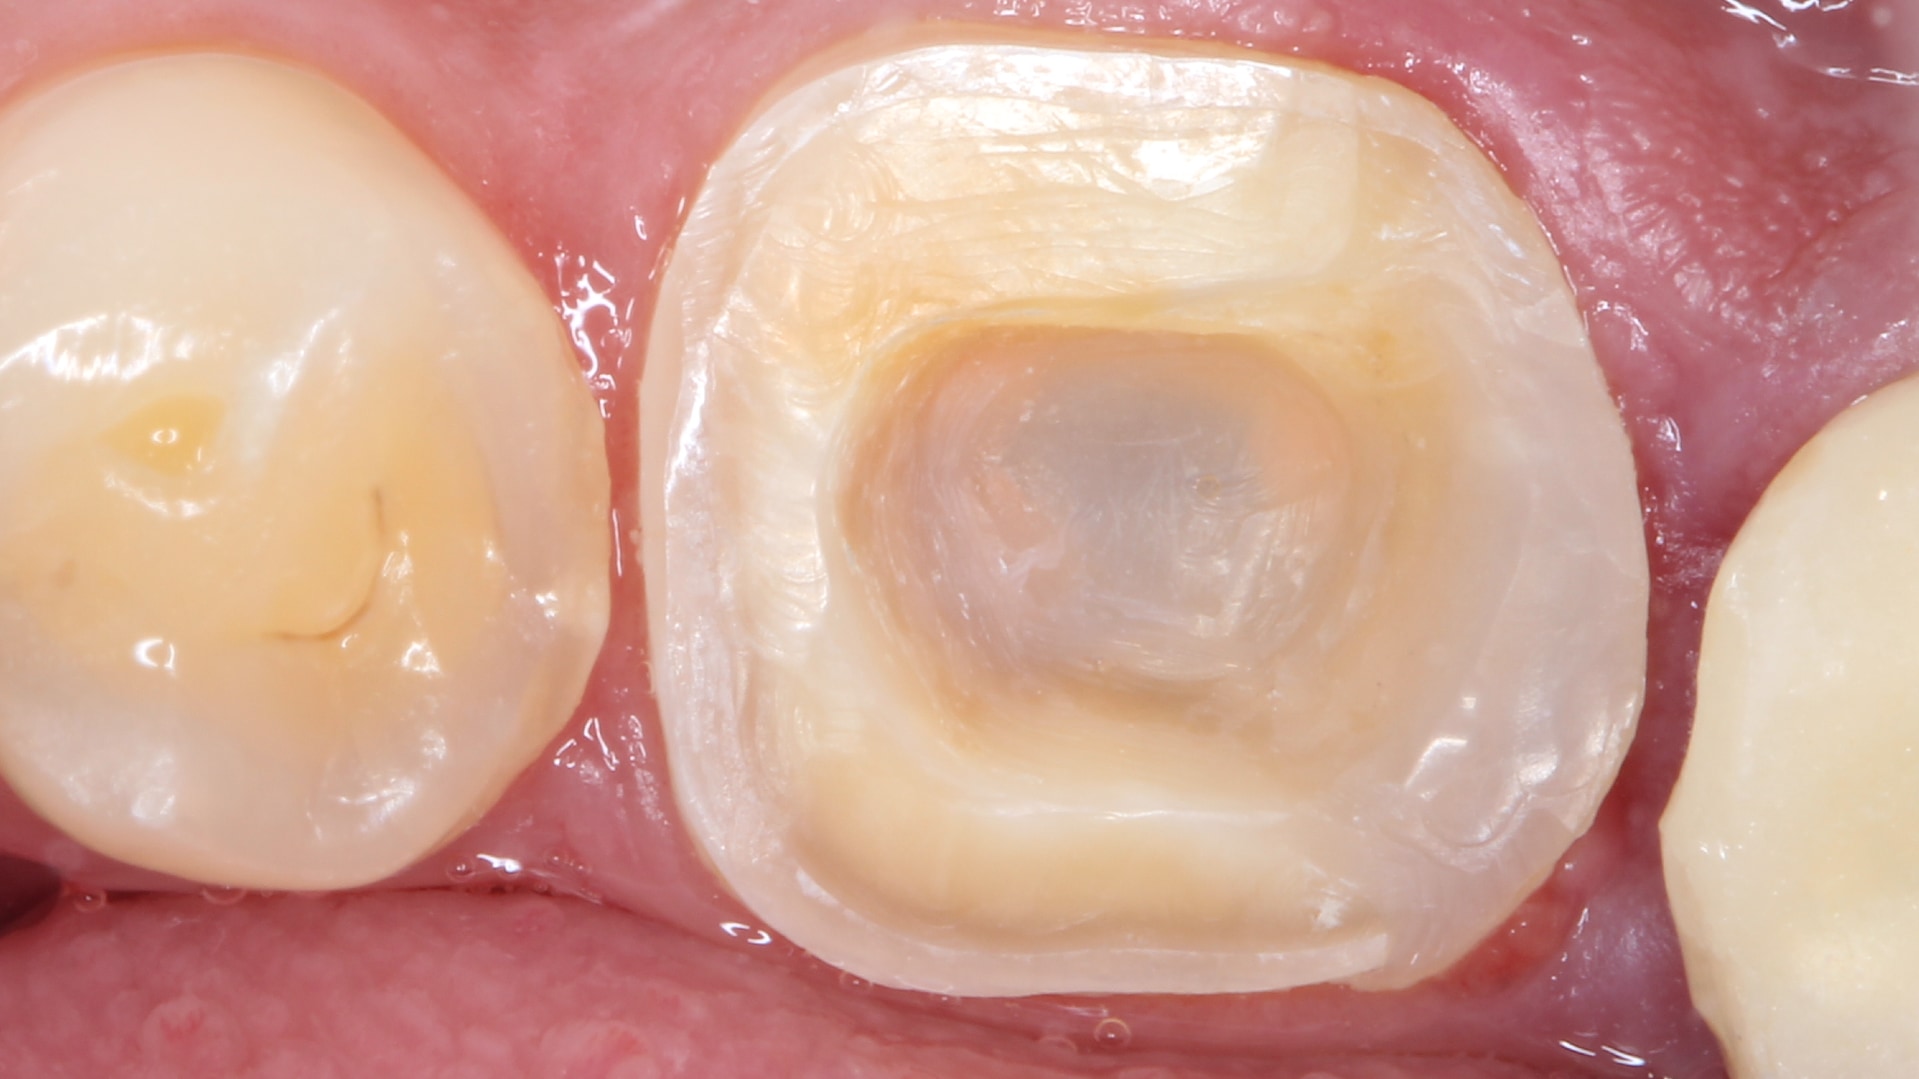

Post-Operative: After impression & mock-up, the final E-Max endocrown was ready for delivery. Proper bonding protocol was applied followed by further finishing & polishing to ensure proper margins and surface smoothness are achieved. The patient was very satisfied with the new restoration and that the symptoms he presented with are finally relieved.